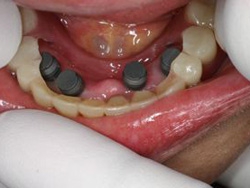

4本埋入終了(このシステムは4本が絶対条件)

当日に義歯の調整に取りかかる。裏側より義歯をくりぬき維持部のカバー(ハウジング)を義歯の内面に埋め込む step1

当日に義歯の調整に取りかかる。裏側より義歯をくりぬき維持部のカバー(ハウジング)を義歯の内面に埋め込む step2

当日に義歯の調整に取りかかる。裏側より義歯をくりぬき維持部のカバー(ハウジング)を義歯の内面に埋め込む step3

当日に義歯の調整に取りかかる。裏側より義歯をくりぬき維持部のカバー(ハウジング)を義歯の内面に埋め込む step4

当日に義歯の調整に取りかかる。裏側より義歯をくりぬき維持部のカバー(ハウジング)を義歯の内面に埋め込む step5

義歯の裏側